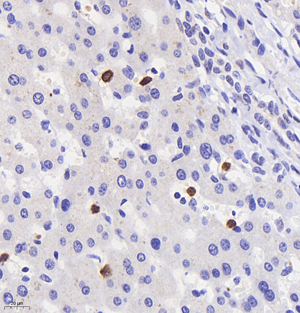

| IHC analysis of mpo (GB11224). Sample: Mouse liver+lps (Paraffin), 4% PFA (G1101) 12-24h. Antigen retrieval: Citrate buffer (pH 6.0) (G1201),98°C,20 min. Blocking buffer: 3% BSA in PBS (GC305010), RT, 30min. Primary antibody: 1: 1000, 4°C overnight. Secondary antibody: HRP Goat Anti-Rabbit lgG (GB23303), 1: 200 RT 1h. |